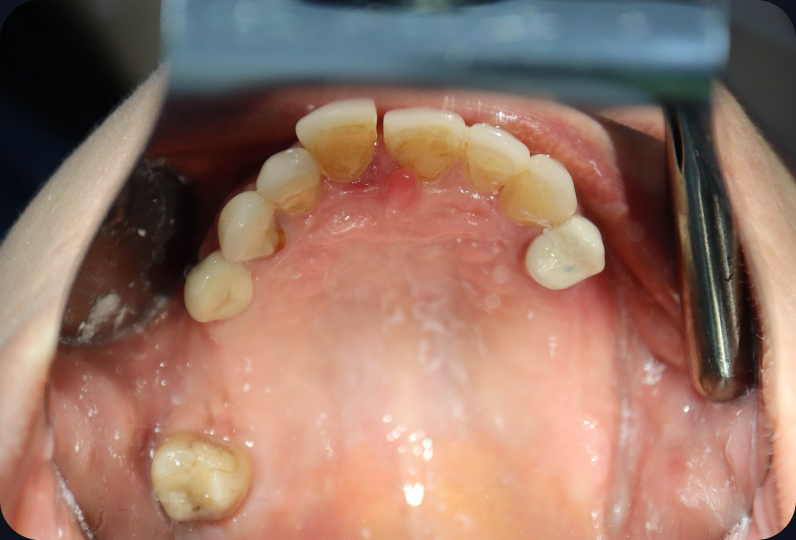

Ситуация до лечения

Пациент обратился с жалобами на эстетические недостатки.

Поставлен диагноз: частичная адентия.

Моляры на верхней челюсти отсутствуют